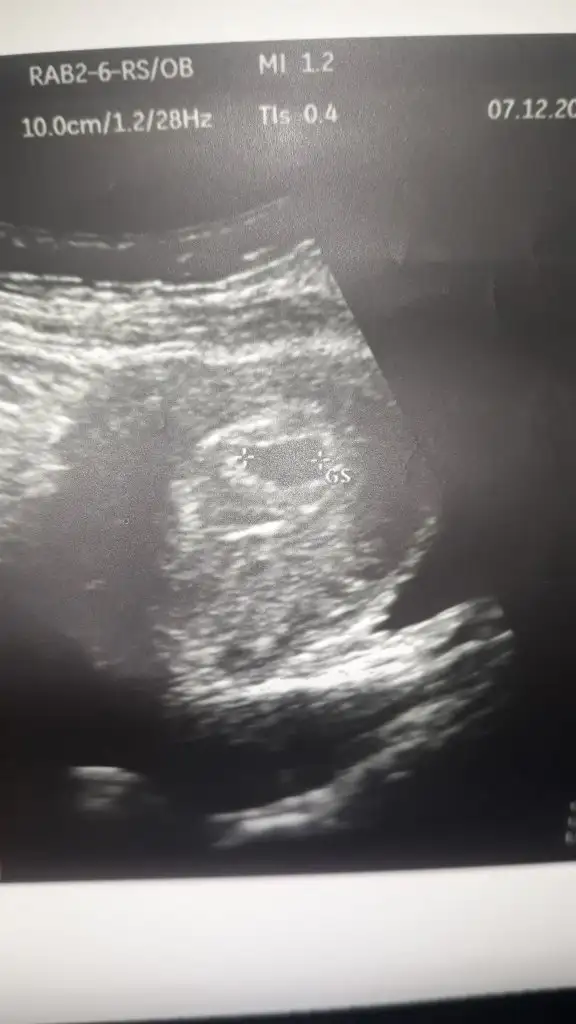

gittim kese gorundu gecen hafta pazartesi kalp atislarini duydum yarin 7. Haftamizdayiz